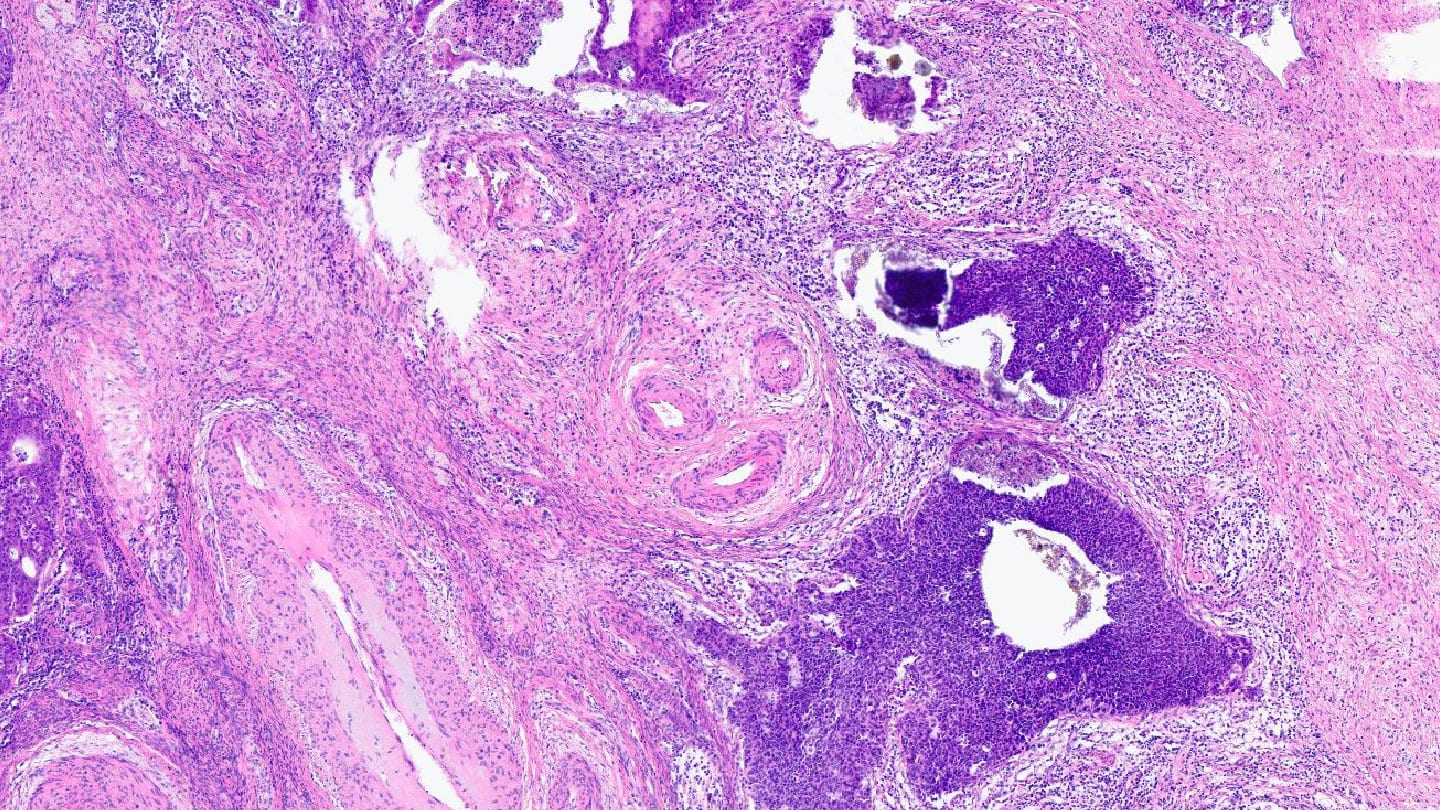

Our image of the month comes from Christine Carreira, who says “Sometimes, beauty hides in unexpected places. In this cervical tumor section, the arrangement of three glands forms an unmistakable smile – reminding us that joy can surface even in the most clinical of settings.”

Christine Carreira, Research Assistant, Histopathology Laboratory, WHO Classification of Tumours Group, Lyon, France